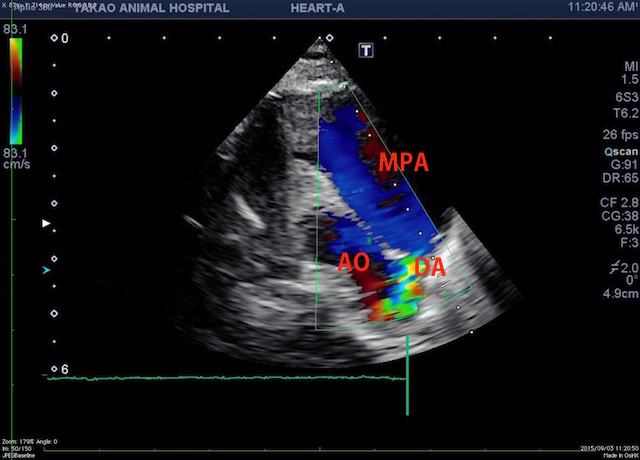

(MPA:主肺動脈 DA:動脈管 AO:大動脈)

若齢の場合でこのような肺高血圧症に至る場合、短絡疾患(心室中隔欠損、心房中隔欠損、動脈管開存症など)は常に念頭に置いて検査が必要ですが、今回のように肺高血圧症が酷いと短絡の血流が見えにくい場合もあります。この症例は主肺動脈から大動脈にかけて血液の短絡を疑う所見が得られました。